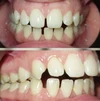

Zirkonyum uygulamalar

Porselen uygulamaları

Laminate veneer